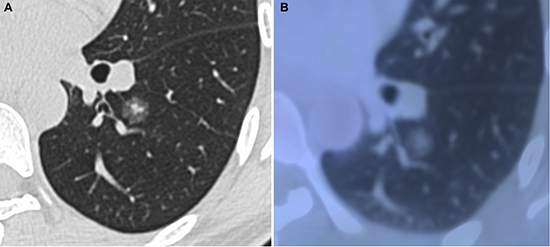

Figure 2: Minimally invasive adenocarcinoma in 40-year-old woman. (A) transverse lung-window HRCT scan demonstrates a round, spiculated, well-defined parenchymal mixed GGN with pleural indentation in the apical segment of the left lower lobe. (B) PET/CT fusion image with perfusion mode shows a 11.9-mm mixed GGN with 0.25 of CTR and 0.81 of SUVmax.